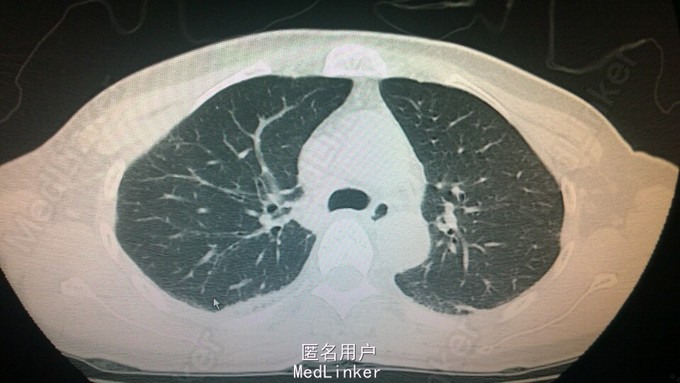

查体:患者全身皮肤变黑、变硬,皮质变薄,皮纹变浅,皮肤附属结构毛囊变少,以右侧前臂远端明显,鼻尖变尖,口唇变薄,双上肢活动受限。听诊双肺呼吸音减弱,未闻及干湿啰音。关节压痛,以右侧腕掌关节明显。余未见异常。 辅助检查:外院:ANA阳性(1:320),胸部CT:双侧肺尖部局部胸壁胸膜增厚。

随访和讨论:全身性硬皮病,是一种以皮肤炎性、变性、增厚和纤维化进而硬化和萎缩为特征的结缔组织病,这是一个全身系统性病,除侵及皮肤外,常累及肺组织,造成肺间质性纤维化,也常累及消化道,侵及食管出现进食哽噎感,后期可累及心脏和肾脏。该病病因不明,主要是对症支持治疗,目前对此干细胞治疗的研究比较火热,国内也有多家医院做干细胞治疗的研究,取得效果较好。该例患者出现活动后气促,完善高分辨率胸部CT的检查,听诊患者双肺底部有细小湿罗音,予头孢美唑钠抗感染治疗,密切观察病情。